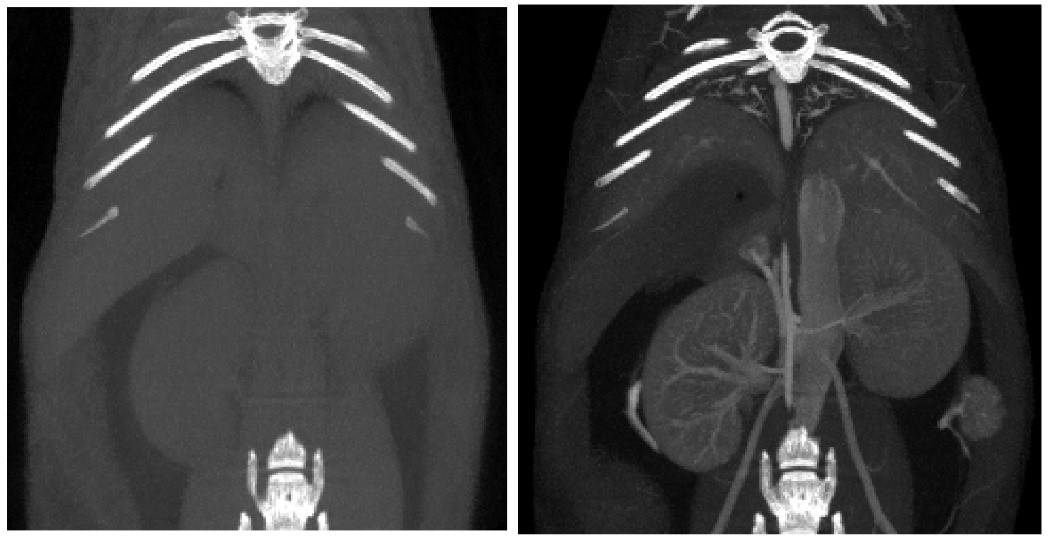

The X-CUBE is our high throughput CT “work horse”. It allows for fast whole body mouse and rat CT imaging at extremely low dose and excellent soft tissue contrast.

(5) Angiography: The developer is rapidly injected into the heart cavity or blood vessel through the cardiac catheter, so that the heart and blood vessel cavity can be developed under CT irradiation. Using contrast media CT, the vascular system and blood-rich tissues and organs can be shown. Ranging from arteries to heart, lungs, kidneys, liver, etc. Provides a better soft tissue contrast for sharper imaging.

Tumor study: Contra-enhanced CT was used to examine liver tumors in living mice: Exitron 12000 was injected, FDK was reconstructed, and the imaging time was 4min, 100μm voxel size.